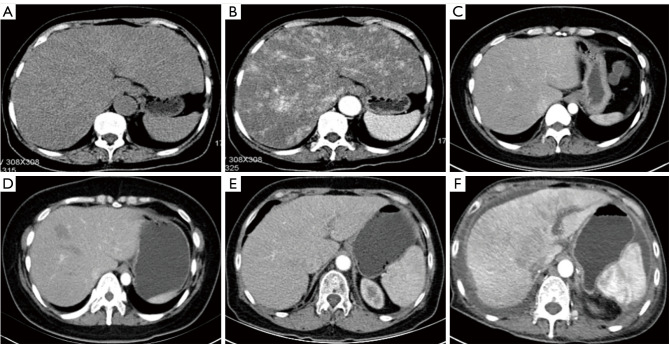

{"title":"药物性肝损伤不同类型及严重程度的ct表现。","authors":"Yao Chen, Yuzhen Xi, Fanfan Zhao, Huanhuan Li, Min Zhou, Yue Xu, Shufeng Fan, Miao Liu","doi":"10.21037/qims-24-2110","DOIUrl":null,"url":null,"abstract":"<p><strong>Background: </strong>Drug-induced liver injury (DILI) has become a major cause of acute liver failure, and its incidence has been increasing steadily in recent years. This study aimed to compare the clinical and computed tomography (CT) imaging features of the variable biochemical damage and severity of DILI to establish a radiological model for predicting high-risk DILI based on CT image features.</p><p><strong>Methods: </strong>The eligible patients with DILI (January 2016 to March 2024) who underwent serum laboratory examination and contrast abdominal CT within 3 months of onset were retrospectively analyzed at Affiliated Xihu Hospital of Hangzhou Medical College (Institution I) and The Second Affiliated Hospital of Zhejiang Chinese Medical University (Institution II). The severity-associated CT features were determined via binomial logistic regression analysis, and the efficacy of the different models were compared. The odds ratios (ORs) and corresponding 95% confidence intervals (CIs) provided were not adjusted.</p><p><strong>Results: </strong>The injury types included hepatocellular (n=68, 45.64%), mixed (n=28, 18.79%), and cholestatic (n=53, 35.57%). The proportion of splenomegaly in patients with cholestatic injury (56.60%) was significantly higher than that in those with hepatocellular (35.71%) and mixed injury (22.06%) (P<0.001). Regarding severity, 127 (85.23%) patients had mild-to-moderate injury, and 22 (14.77%) had severe-to-fatal injury or required liver transplantation (LT). Injury severity was independently associated with quantitative liver-spleen contrast (Q-LSC) (OR =0.002; 95% CI: 0.00-0.13), and ascites (OR =70.83; 95% CI: 16.34-306.99). The prediction of the new model employing Q-LSC and ascites for high-risk DILI demonstrated excellent performance [area under the receiver operating characteristic (ROC) curve (AUC) =0.929; sensitivity=0.818; specificity =0.953].</p><p><strong>Conclusions: </strong>Statistical differences are observed in the serum biomarkers of DILI according to varying biochemical damage and degree of severity. Q-LSC and ascites were associated with the severity of DILI, and a combined model incorporating Q-LSC and ascites can effectively predict high-risk DILI.</p>","PeriodicalId":54267,"journal":{"name":"Quantitative Imaging in Medicine and Surgery","volume":"15 9","pages":"8553-8566"},"PeriodicalIF":2.3000,"publicationDate":"2025-09-01","publicationTypes":"Journal Article","fieldsOfStudy":null,"isOpenAccess":false,"openAccessPdf":"https://www.ncbi.nlm.nih.gov/pmc/articles/PMC12397697/pdf/","citationCount":"0","resultStr":"{\"title\":\"Computed tomography manifestations of drug-induced liver injury according to type and severity of injury.\",\"authors\":\"Yao Chen, Yuzhen Xi, Fanfan Zhao, Huanhuan Li, Min Zhou, Yue Xu, Shufeng Fan, Miao Liu\",\"doi\":\"10.21037/qims-24-2110\",\"DOIUrl\":null,\"url\":null,\"abstract\":\"<p><strong>Background: </strong>Drug-induced liver injury (DILI) has become a major cause of acute liver failure, and its incidence has been increasing steadily in recent years. This study aimed to compare the clinical and computed tomography (CT) imaging features of the variable biochemical damage and severity of DILI to establish a radiological model for predicting high-risk DILI based on CT image features.</p><p><strong>Methods: </strong>The eligible patients with DILI (January 2016 to March 2024) who underwent serum laboratory examination and contrast abdominal CT within 3 months of onset were retrospectively analyzed at Affiliated Xihu Hospital of Hangzhou Medical College (Institution I) and The Second Affiliated Hospital of Zhejiang Chinese Medical University (Institution II). The severity-associated CT features were determined via binomial logistic regression analysis, and the efficacy of the different models were compared. The odds ratios (ORs) and corresponding 95% confidence intervals (CIs) provided were not adjusted.</p><p><strong>Results: </strong>The injury types included hepatocellular (n=68, 45.64%), mixed (n=28, 18.79%), and cholestatic (n=53, 35.57%). The proportion of splenomegaly in patients with cholestatic injury (56.60%) was significantly higher than that in those with hepatocellular (35.71%) and mixed injury (22.06%) (P<0.001). Regarding severity, 127 (85.23%) patients had mild-to-moderate injury, and 22 (14.77%) had severe-to-fatal injury or required liver transplantation (LT). Injury severity was independently associated with quantitative liver-spleen contrast (Q-LSC) (OR =0.002; 95% CI: 0.00-0.13), and ascites (OR =70.83; 95% CI: 16.34-306.99). The prediction of the new model employing Q-LSC and ascites for high-risk DILI demonstrated excellent performance [area under the receiver operating characteristic (ROC) curve (AUC) =0.929; sensitivity=0.818; specificity =0.953].</p><p><strong>Conclusions: </strong>Statistical differences are observed in the serum biomarkers of DILI according to varying biochemical damage and degree of severity. Q-LSC and ascites were associated with the severity of DILI, and a combined model incorporating Q-LSC and ascites can effectively predict high-risk DILI.</p>\",\"PeriodicalId\":54267,\"journal\":{\"name\":\"Quantitative Imaging in Medicine and Surgery\",\"volume\":\"15 9\",\"pages\":\"8553-8566\"},\"PeriodicalIF\":2.3000,\"publicationDate\":\"2025-09-01\",\"publicationTypes\":\"Journal Article\",\"fieldsOfStudy\":null,\"isOpenAccess\":false,\"openAccessPdf\":\"https://www.ncbi.nlm.nih.gov/pmc/articles/PMC12397697/pdf/\",\"citationCount\":\"0\",\"resultStr\":null,\"platform\":\"Semanticscholar\",\"paperid\":null,\"PeriodicalName\":\"Quantitative Imaging in Medicine and Surgery\",\"FirstCategoryId\":\"3\",\"ListUrlMain\":\"https://doi.org/10.21037/qims-24-2110\",\"RegionNum\":2,\"RegionCategory\":\"医学\",\"ArticlePicture\":[],\"TitleCN\":null,\"AbstractTextCN\":null,\"PMCID\":null,\"EPubDate\":\"2025/8/11 0:00:00\",\"PubModel\":\"Epub\",\"JCR\":\"Q2\",\"JCRName\":\"RADIOLOGY, NUCLEAR MEDICINE & MEDICAL IMAGING\",\"Score\":null,\"Total\":0}","platform":"Semanticscholar","paperid":null,"PeriodicalName":"Quantitative Imaging in Medicine and Surgery","FirstCategoryId":"3","ListUrlMain":"https://doi.org/10.21037/qims-24-2110","RegionNum":2,"RegionCategory":"医学","ArticlePicture":[],"TitleCN":null,"AbstractTextCN":null,"PMCID":null,"EPubDate":"2025/8/11 0:00:00","PubModel":"Epub","JCR":"Q2","JCRName":"RADIOLOGY, NUCLEAR MEDICINE & MEDICAL IMAGING","Score":null,"Total":0}

Background: Drug-induced liver injury (DILI) has become a major cause of acute liver failure, and its incidence has been increasing steadily in recent years. This study aimed to compare the clinical and computed tomography (CT) imaging features of the variable biochemical damage and severity of DILI to establish a radiological model for predicting high-risk DILI based on CT image features.

Methods: The eligible patients with DILI (January 2016 to March 2024) who underwent serum laboratory examination and contrast abdominal CT within 3 months of onset were retrospectively analyzed at Affiliated Xihu Hospital of Hangzhou Medical College (Institution I) and The Second Affiliated Hospital of Zhejiang Chinese Medical University (Institution II). The severity-associated CT features were determined via binomial logistic regression analysis, and the efficacy of the different models were compared. The odds ratios (ORs) and corresponding 95% confidence intervals (CIs) provided were not adjusted.

Results: The injury types included hepatocellular (n=68, 45.64%), mixed (n=28, 18.79%), and cholestatic (n=53, 35.57%). The proportion of splenomegaly in patients with cholestatic injury (56.60%) was significantly higher than that in those with hepatocellular (35.71%) and mixed injury (22.06%) (P<0.001). Regarding severity, 127 (85.23%) patients had mild-to-moderate injury, and 22 (14.77%) had severe-to-fatal injury or required liver transplantation (LT). Injury severity was independently associated with quantitative liver-spleen contrast (Q-LSC) (OR =0.002; 95% CI: 0.00-0.13), and ascites (OR =70.83; 95% CI: 16.34-306.99). The prediction of the new model employing Q-LSC and ascites for high-risk DILI demonstrated excellent performance [area under the receiver operating characteristic (ROC) curve (AUC) =0.929; sensitivity=0.818; specificity =0.953].

Conclusions: Statistical differences are observed in the serum biomarkers of DILI according to varying biochemical damage and degree of severity. Q-LSC and ascites were associated with the severity of DILI, and a combined model incorporating Q-LSC and ascites can effectively predict high-risk DILI.